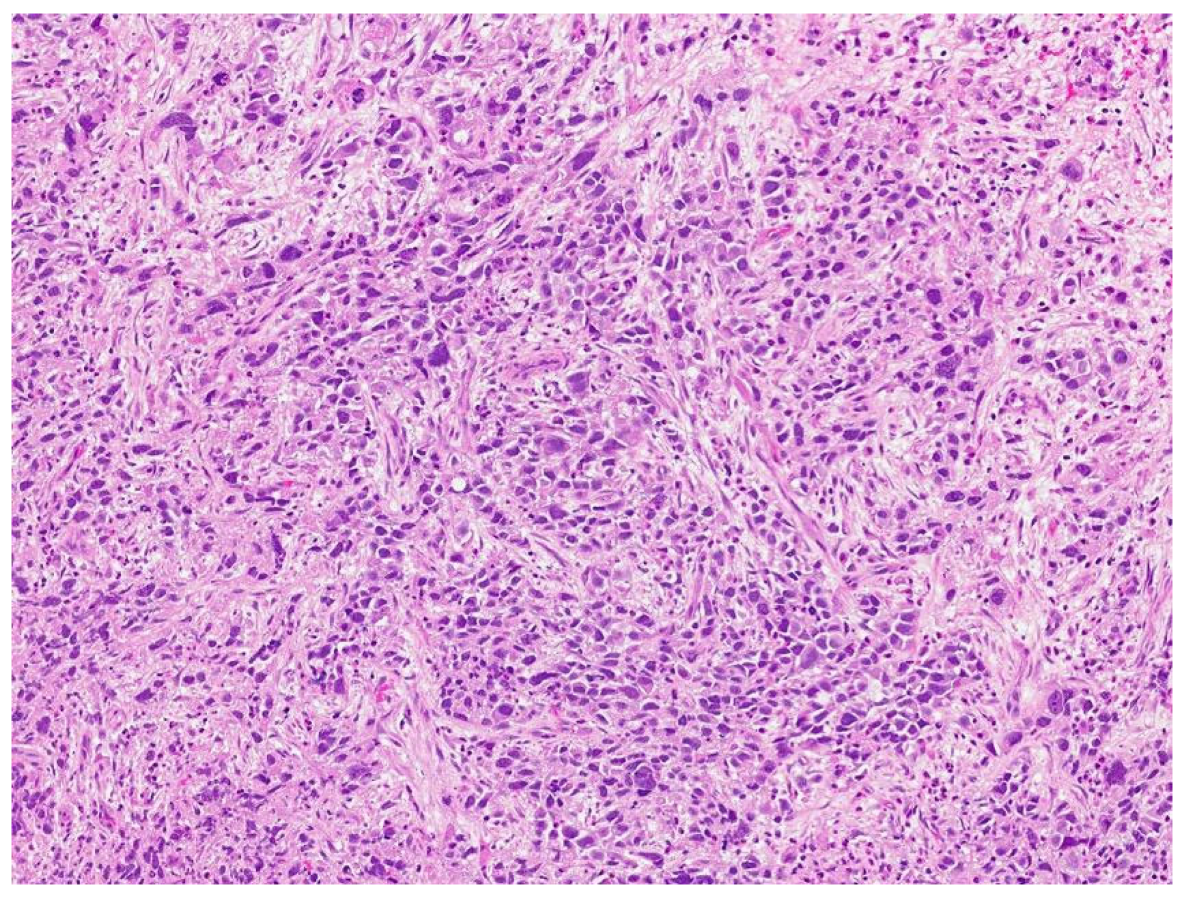

Review of pathology indicated S-YST (Figure 7): SALL4, focally positive; GPC3, weakly and focally positive (Figure 8). CD117 and OCT3/4 were negative in tumor cells, i(12p) was positive.

Figure 7.

Sarcomatoid yolk sac tumor with pleomorphic epithelioid and spindle cells, hematoxylin, and eosin stain.